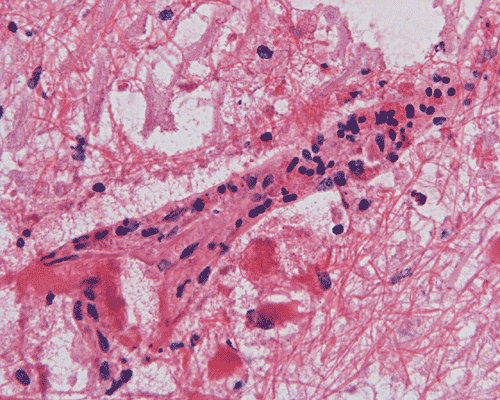

G. Squash |

Panel A to E are MR images. Panel F and G are taken from intraoperative cytologic preparation. Panel H to M are taken from frozen section. Panel N and O are from paraffin section. These sections are stained by hematoxylin-eosin stain. Panel P is immunohistochemistry for neurofilament proteins. Panel Q is stained by Luxol fast blue-Periodic acid Schiff (LFB-PAS) stain.

| DIAGNOSIS: Eosinophilic myelitis. |

Pathology of eosinophilic myelitis

Eosinophilic myelitis is featured by lymphocytic infiltration accompanied by a varying intensity of eosinophils. Both the myelin and axons may be damaged. Axonal spheroids can be seen and indicate primary axonal damage rather than secondary damage following demyelination 14, 15. Destruction of axons in the lesion may well explain the relatively poor recovery of this condition. There is increase in eosinophils in CSF in the our under discussion. However, the CSF studies are normal in two previous studies 14, 15.

The eosinophils play an important role in causing the damages. Infiltration by eosinophils and depositions of activated products of eosinophils are commonly seen in atopic disorders, such as atopic bronchial asthma, allergic rhinitis and atopic dermatitis. The presence of atopic diathesis as well as eosinophilic cationic protein deposition suggests that atopy may represent one of the risk factors for developing eosinophilic myelitis. Eosinophilic cationic protein is one of the neurotoxic proteins released by activated eosinophils Eosinophil cationic protein and other products of eosinophils such as major basic protein have been shown to be neurotoxic. The infiltrating eosinophils may therefore well contribute to the neural damage.

In addition to eosinophils, predominant CD8 T-lymphocytes infiltration is commonly observed 14. Selective infiltration of CD8 T-lymphocytes into the parenchyma, may suggest the critical pathogenic role of these cells, such as a cytotoxic role rather than a secondary suppressive one. In atopic disorders, acute lesions are characterized by predominant CD4 T-lymphocytes infiltration over CD8 T-lymphocytes infiltration, while CD8 T-lymphocytes predominate in chronic lesions. Therefore, the predominant infiltration of CD8 T-lymphocytes seen in the spinal cord may reflect the chronic nature of the lesions.